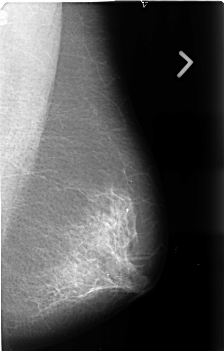

B_3387_1.RIGHT_MLO

FILE: B_3387_1.RIGHT_MLO.OVERLAY

TOTAL_ABNORMALITIES 1

ABNORMALITY 1

LESION_TYPE MASS SHAPE IRREGULAR MARGINS MICROLOBULATED-ILL_DEFINED

ASSESSMENT 5

SUBTLETY 5

PATHOLOGY MALIGNANT